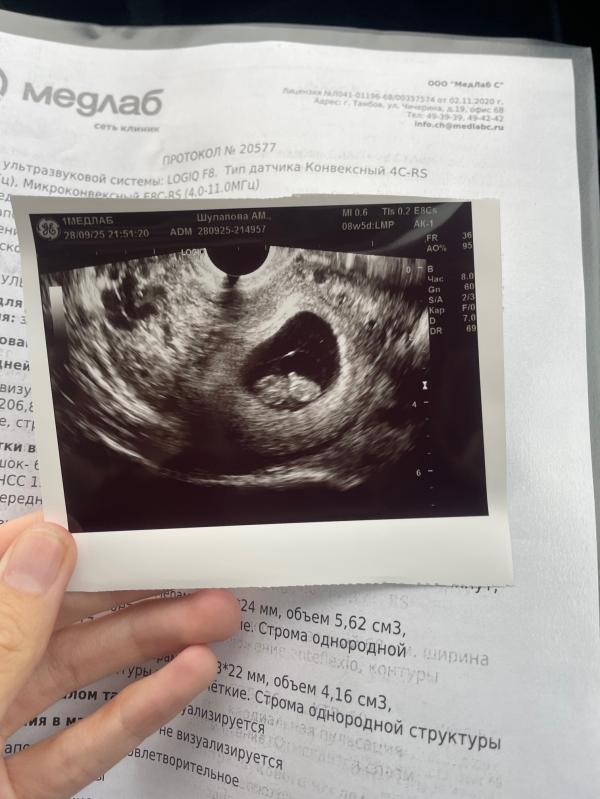

post image

Мои 8.5 недель ♥️

Прям мини мини человек 🤭